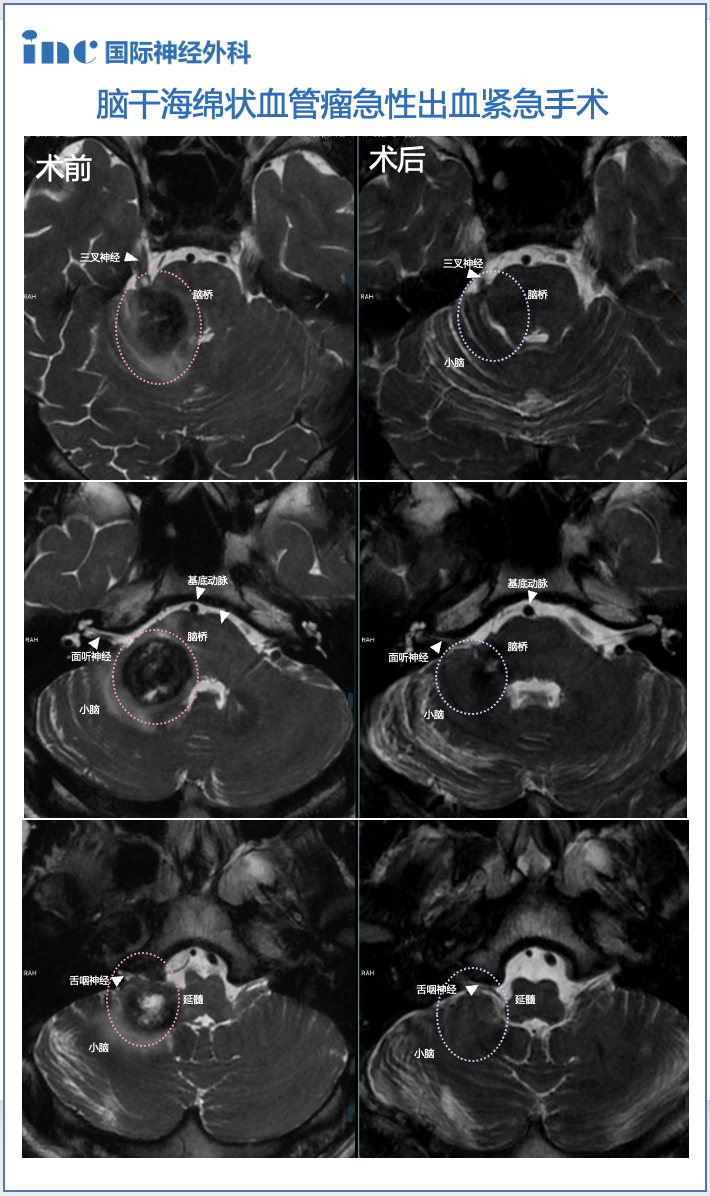

由于脑干内密集分布颅神经核团、上下行纤维束及网状纤维,即使较小病变也可导致严重复杂的症状。中脑病变可因出血阻塞中脑导水管而引起头痛、呕吐及意识障碍;脑桥病变可影响三叉神经、外展神经和面神经核团,导致面部感觉障碍、眼球外展障碍及面瘫;延髓病变则可引发呼吸循环障碍、顽固性呃逆及胃肠道出血。

脑干海绵状血管瘤易反复出血,为最大限度挽救生命并提高生活质量,通常采用显微外科手术结合精确影像学诊断进行治疗。治疗过程中需合理选择手术入路,运用显微外科技术安全切除病灶,将再出血风险降至最低,这是治疗成功的关键。脑干海绵状血管瘤手术应以全切病灶、防止出血和再出血,并尽量减少对正常脑干实质的损伤为目标。

鹏鹏暑假期间突发头晕、耳鸣、面部麻木等症状,检查发现脑干及右侧桥臂区异常信号,疑似海绵状血管瘤。在医生建议下采取保守治疗,但仅10天后头晕加重,出现行走不稳和视物重影,经急诊120转至北京。医生告知需要手术,但风险高且术后可能出现并发症。此时鹏鹏右耳听力几乎丧失,这个年轻生命该如何绽放青春光彩?“我们全程通过120医疗转运,症状特别重。手术很顺利,选择是正确的。巴教授手术后第二天头晕消失,症状逐渐减轻,一天比一天好转。”

19岁少年阿朔因头痛头昏检查发现脑干延髓海绵状血管瘤。“一个人难以接受这个事实,刚确诊时非常痛苦煎熬,书读不进去,饭也吃不下……”这个阳光爱笑的大男孩陷入人生低谷:“那一刻觉得时间过得很慢,希望要么尽快手术,要么事情尽快有定论。”勇敢抗争的少年和全力支持的父母在多方求医后找到INC巴特朗菲教授。巴教授在国内示范手术中全程直播完成病灶全切。术后一个月,阿朔重返大学校园,恢复正常学习和生活。